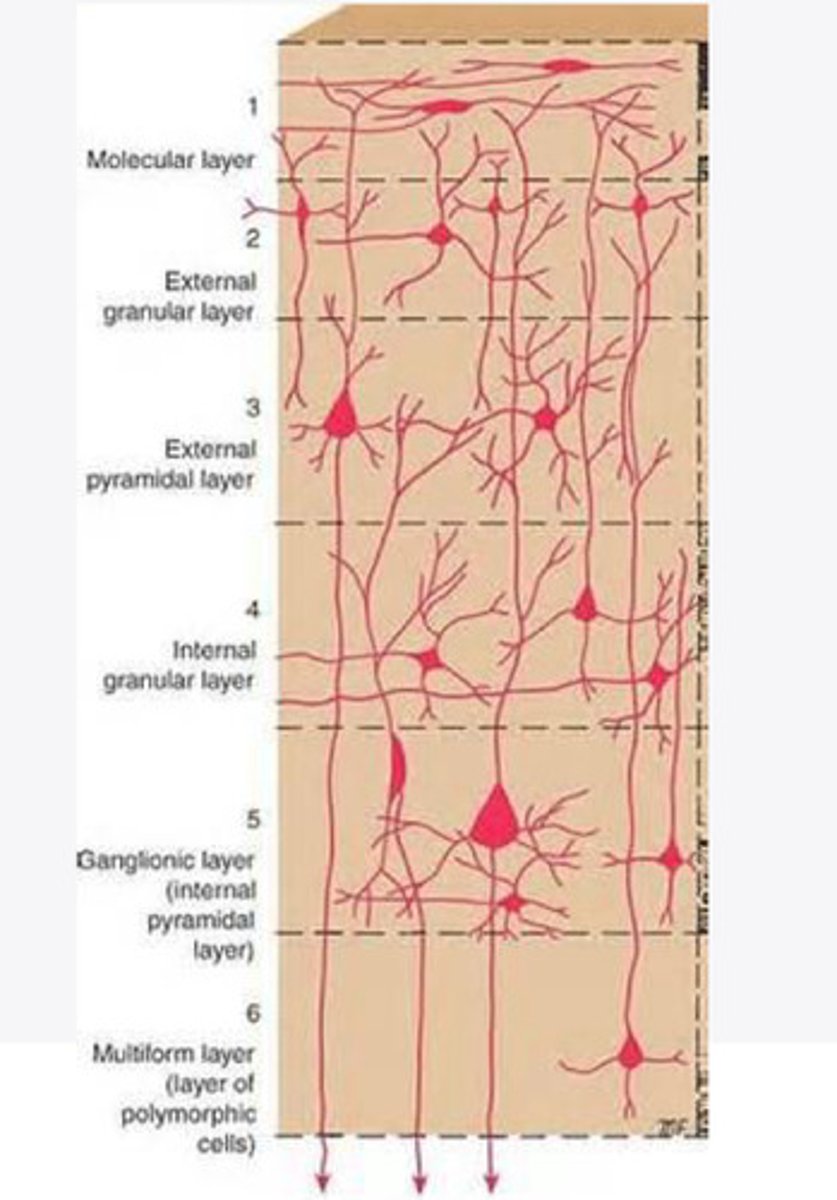

divided into 6 distinct layers, due to varying densities of cell body types within each layer

The cortex of the brain is divided into how many layers? Why is it divided into layers?

Layers of the cortex of the brain pic

2 and 4

What are the layers of the cortex that are associated with input?

3 and 5

What are the layers of the cortex that are associated with output?

molecular layer

What is the name of Layer 1 of the cortex of the brain?

very few cells

Does Layer 1 of the cortex have a lot or few cells?

receives dendrites from internal layers so it may actually function as a coordinating center where layers can communicate action

What does Layer 1 of the cortex do?

1

Every layer sends densities to Layer ____?

1

What layer serves as the "water cooler" of the brain?

external granular layer

What is the name for layer 2 of the cortex of the brain?

receives input from other cortical regions

What is the function of Layer 2 of the Cortex of the brain?

Stellate

What type of cells (stellate/pyramidal) would be most concentrated in Layer 2?

external pyramidal layer

What is the name for layer 3 of the cortex of the brain?

sends output to the other cortical layers

What is the function of Layer 3 of the cortex of the brain?

pyramidal

What type of cells (stellate/pyramidal) would be most concentrated in Layer 3 of the brain?

Layers 2 and 3

What layers are associated with association and commissural fibers?

Layer 3 - axons of cell bodies

Layer 2 - synapse into target areas in Layer 2

What part of the axons is in Layer 2/ in layer 3?

Layer 3 - external pyramidal layer

All axonal cel bodies for association and commissural fibers lie within what layer of the Cortex of the brain?

internal granular

** or called the striate cortex because it is so thick that you can see a line through this layer even in unstrained brain slides

What is the name for the 4th layer of the cortex of the brain?

receives input from the thalamus, geniculocortical layer, and other brainstem areas

What is the function for the 4th layer of the Cortex of the brain?

very thick within the vision, auditory, and somatosensory areas

Is Layer 4 thick or thin within SENSORY areas of the cortex?

Internal pyramidal

What is the name for Layer 5 of the cortex of the brain?

sends axons to the brainstem (corticobulbar) and spinal cord (corticospinal)

What is the function of Layer 5 of the cortex of the brain?

in motor areas of the cortex?

Where is layer 5 very thick in the brain?

the frontal lobe -- very motor heavy

What lobe of the brain will have a thick layer 5 of the cortex of the brain?

the multiform layer

What is the name of layer 6 of the cortex of the brain?

-sends axons back to the thalamus through corticogeniculate fibers

-modulates what information the thalamus sends to the cortex to control the strength of the signal received and modulate what you pay attention to

What is the function of layer 6 of the cortex of the brain?

no

Is layer 6 a motor layer?